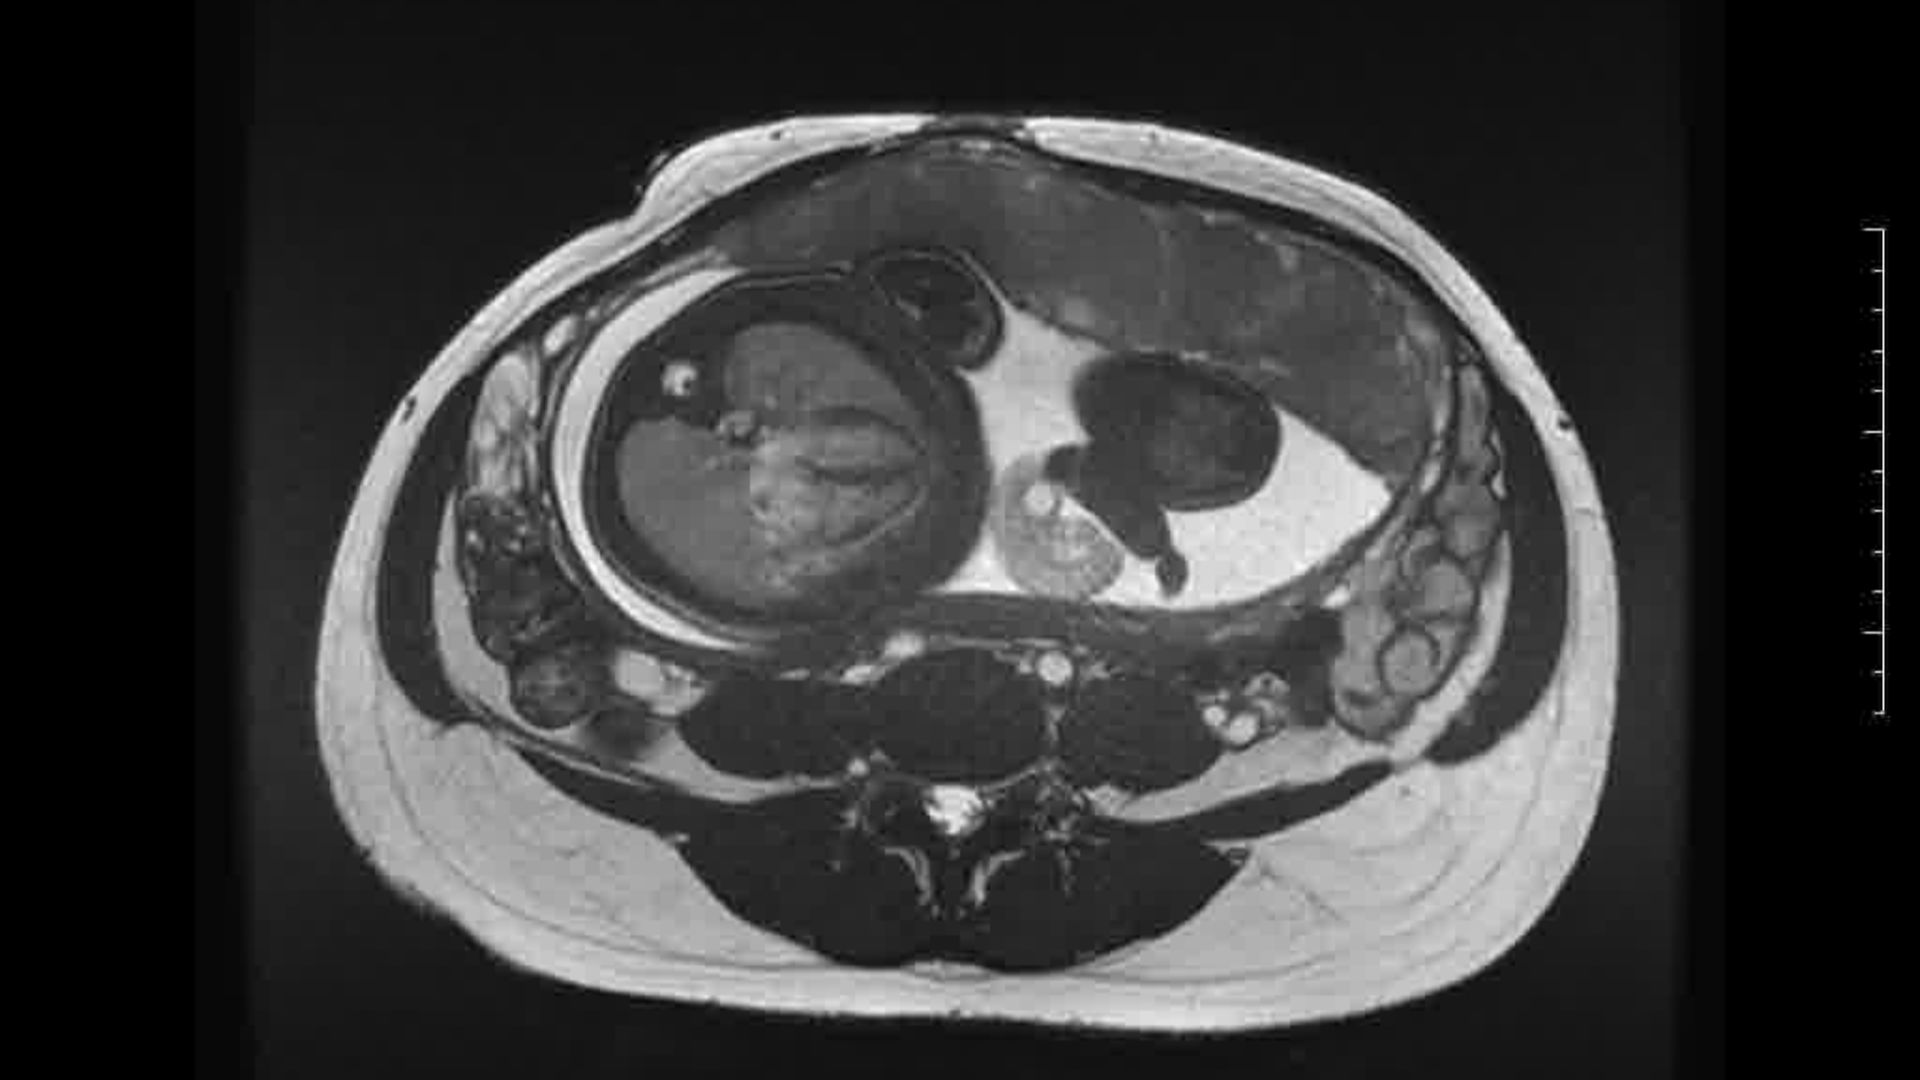

L’Université Paris Cité franchit une nouvelle étape dans le domaine de l’imagerie médicale anténatale avec l’acquisition d’un système d’Imagerie par Résonance Magnétique (IRM) 1,5T ARTIST™ de GE HealthCare. Cet équipement de pointe renforce les capacités de la Plateforme LUMIERE à l’hôpital Necker-Enfants malades, plateforme intégrée de soins, de recherche clinique et d’enseignement en imagerie médicale de la femme enceinte, du fœtus et du placenta.

Depuis 2020, la Plateforme LUMIERE offre aux femmes enceintes volontaires, entre 16 et 36 semaines d’aménorrhée et suivies à l’hôpital Necker-Enfants malades, la possibilité de participer activement à l’avancée de la recherche en médecine fœtale, tout en bénéficiant d’une IRM fœtale au cours de leur grossesse, réalisée dans un cadre sécurisé et encadré.

L’inclusion de ces patientes, depuis leur accueil jusqu’à la réalisation des examens d’imagerie, puis l’analyse des images et l’interprétation des résultats par des équipes expertes, enrichit une base de données structurée, unique au monde, au service de la recherche et de l’innovation en imagerie anténatale et en médecine fœtale.